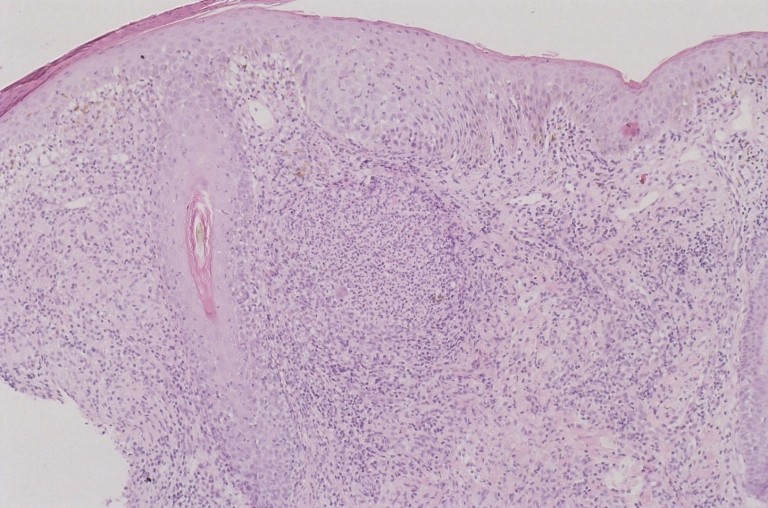

Histologisch beeld van lesionale huid: hoog dermaal granulomateus infiltraat met omliggend veel lymfocyten. Infiltraat met name perifolliculair aanwezig. (2 of 3 mm biopt volstaat; cave keloid vorming en risico op postinflammatoire hyper-of hypopigmentatie).